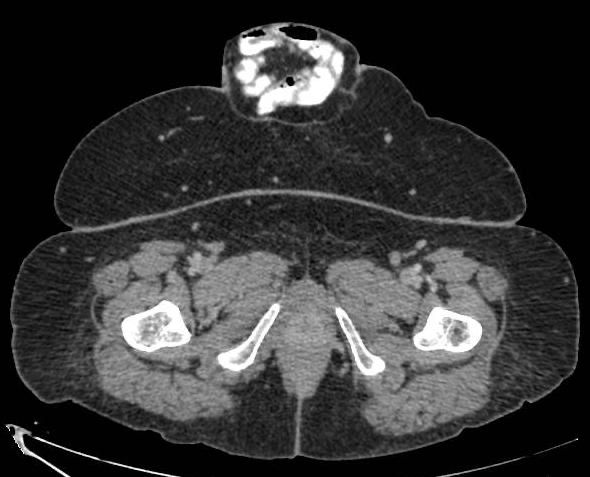

استحدث مستشفى اليمامة أحد مكونات تجمع الرياض الصحي الثاني عيادة النزيف الرحمي وهي إحدى العيادات المتخصصة في أمراض النساء والولادة.

وبين مستشفى اليمامة أن العيادة تستقبل الإحالات من المراكز الصحية أو المستشفيات من داخل أو خارج مدينة الرياض وترتكز على الزيارة الواحدة عكس العيادات الروتينية، حيث يتم تقييم الحالة الصحية المرضية وطلب الفحوصات والتحاليل المخبرية والأشعة وأخذ العينات اللازمة بنفس الزيارة، ومن ثم يحدد خطة العلاج .